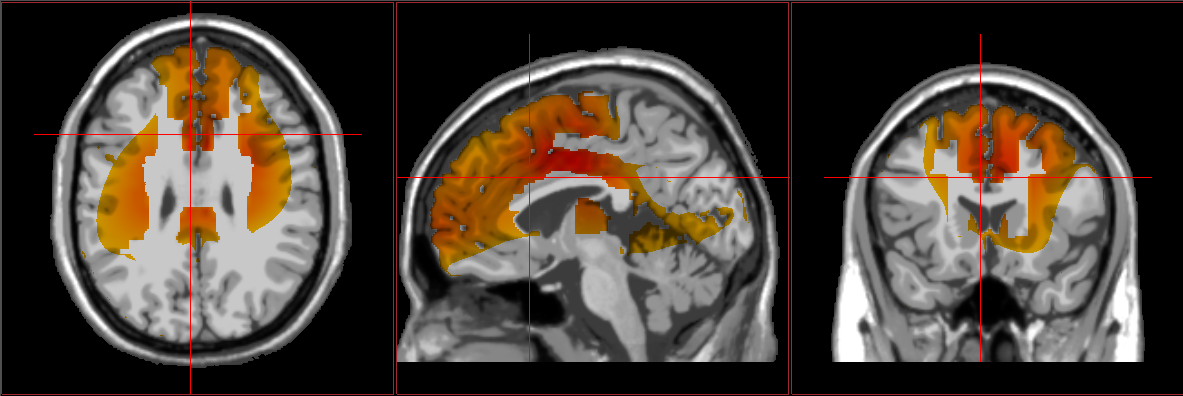

EEG brain scans showing typical results from autism loreta neurofeedback showing signs of autism Autism / spectrum results from loreta neurofeedback

Atypical connectivity patterns within the brain seem to explain some of the challenges experienced by those with ASD. EEG and fMRI imaging demonstrate a surplus of synapses and connections between certain regions, which can make it difficult for a person to switch between tasks and ideas. This might underlie the repetitive and restrictive behaviors often exhibited by those with ASD. Hyperconnectivity and inefficient communication between neurons can also affect other important processes such as motor control, interpretation of social cues, and language production/analysis.

Furthermore, the brains of those diagnosed with ASD often show reduced activation levels within imitation-related brain areas when compared to individuals without ASD. Limited functioning of these areas is thought to contribute to a variety of ASD symptoms, especially those related to social interactions.

- Datko, Pineda, and Muller (2018) researched whether neurofeedback training targeting sensorimotor mu-rhythm could improve imitation-related brain activation in children with high-functioning ASD. They used a control group of similarly aged children without ASD diagnoses for comparison. The outcomes showed that this form of neurofeedback did in fact increase activation of mirror neurons during imitation tasks, in line with observable neurophysiological changes within the neurofeedback-trained regions. This suggests that neurofeedback focused on sensorimotor mu training could help improve social functioning for individuals on the spectrum.

- Datko, M., Pineda, J. A., & Müller, R. (2018). Positive effects of neurofeedback on autism symptoms correlate with brain activation during imitation and observation. European Journal of Neuroscience, 47, 579-591. doi:10.1111/ejn.13551